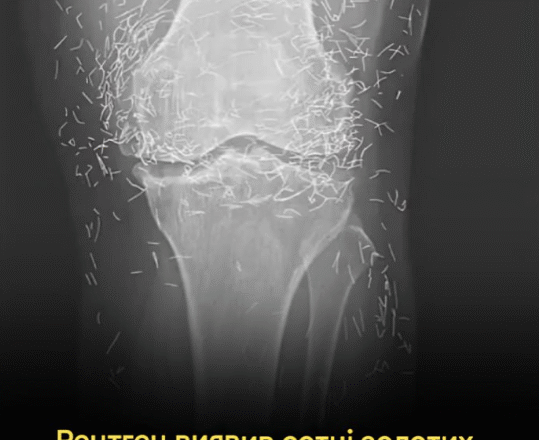

Коли лікарі досліджували рентгенівський знімок колін літньої жінки, яка страждала від сильного болю в суглобах, вони знайшли золоту жилу: сотні крихітних золотих голок для акупунктури, залишених у її тканинах.

У звіті йдеться, що під час лікування жінки акупунктурою голки, які, ймовірно, були виготовлені з золота, були навмисно залишені в її тканинах для подальшої стимуляції.

Це також може ускладнити для лікаря читання рентгенівського знімка. «Голки можуть приховувати деякі анатомічні органи», – сказав Гермазі.